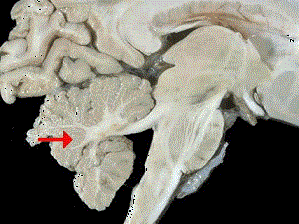

如图箭头所示为大脑哪个部位 ( ) A、脑干B、额叶C、枕叶D、小脑E、顶叶

问题 如图箭头所示为大脑哪个部位 ( )

选项 A、脑干 B、额叶 C、枕叶 D、小脑 E、顶叶

答案 D